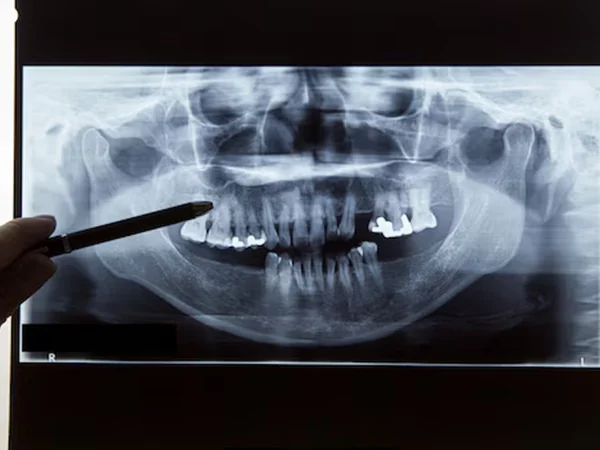

Here at Gelos Dentistry in Mohali and Zirakpur, we take our time with the planning. Using tools like our in-house 3D CBCT scanner, 5D intraoral scans, and Digital Smile Design, we create a custom plan that actually fits your life and your mouth.

Think of full mouth rehab (or full mouth reconstruction) as giving your mouth a complete reset. Rather than treating each problem separately, we look at the big picture how all your teeth work together when you bite, chew, and smile.